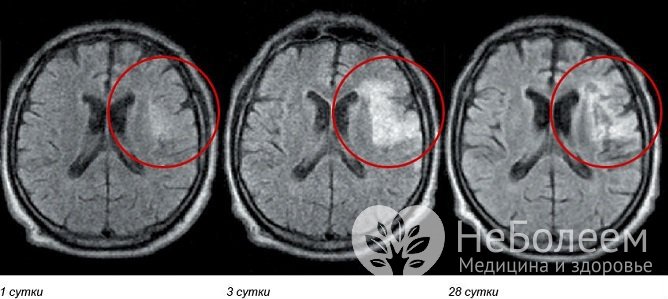

Наиболее тяжелыми являются первые две–три недели после кровоизлияния в мозг. Тяжесть состояния в этом периоде обусловлена образованием гематомы и прогрессирующим отеком мозга. К концу первого месяца общемозговые симптомы регрессируют, более выраженными становятся обусловленные очаговым поражением, от которых и зависит дальнейшее течение заболевания, осложнения и последствия кровоизлияния в мозг.